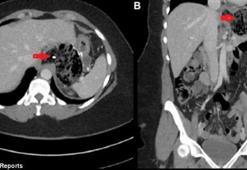

Saç yeme hastalığı: Rapunzel sendromuDoktorlar ismi belirtilmeyen bir hastanın midesinde buldukları şey karşısında hayrete düştü. 37 yaşındaki hasta karın ağrısı, iştah kaybı ve kusma şikayetleriyle hastaneye geldi.

11.10.2017Genel Sağlık